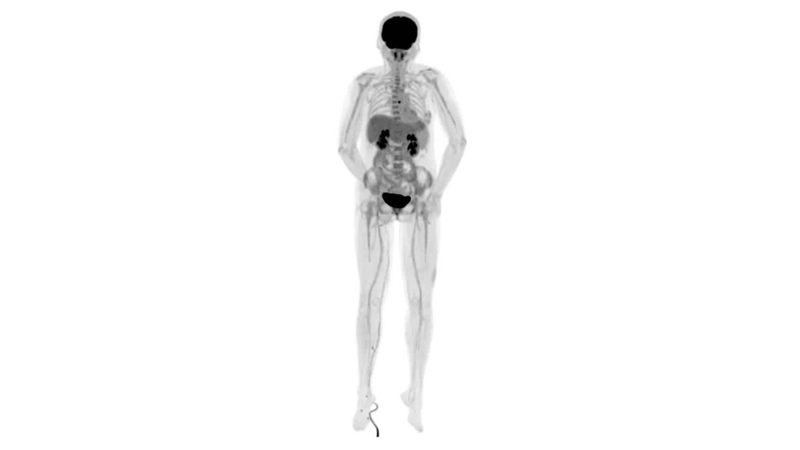

直腸癌

男,45歲,直腸癌術后9個月,發(fā)現(xiàn)肺占位

臨床診斷:直腸區(qū)術后改變,復發(fā)伴骶骨受累,雙肺多發(fā)轉(zhuǎn)移